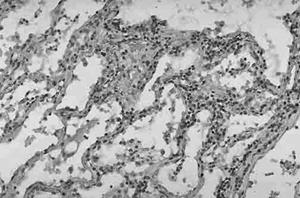

急性感染時大多數病灶發生在肺部,其他臟器偶也有膿腫。亞急性感染時,肺部膿腫趨向擴散,可遍及皮膚、皮下組織、腦膜、腦、眼、心 肝、腎、脾 骨、前列腺 滑膜和淋巴結等處。急性膿腫的特點是外周有出血,中間帶為大量的中性多核白細胞浸潤,中心區為壞死性碎片 其中含有大量的2~3個核的巨大組織細胞。明顯的核破裂是組織學的重要特徵。慢性感染時病灶中心見乾酪樣壞死,由單核細胞、漿細胞浸潤以及肉芽組織形成,並無鈣化現象。